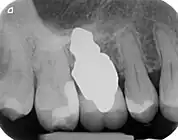

A new attempt was made by Pirker et al 2004 in a human trial with root analogue zirconia implants, but this time by applying differentiated osseoingration on the surface. In 2011 he reported 90% success rate with this method in a 2.5 year human trial.[16]

- 1 2 3 Pirker, W; Wiedemann, D; Lidauer, A; Kocher, A (2011). "Immediate, single stage, truly anatomic zirconia implant in lower molar replacement: a case report with 2.5 years follow-up". International Journal of Oral and Maxillofacial Surgery. 40 (2): 212–6. doi:10.1016/j.ijom.2010.08.003. PMID 20833511.